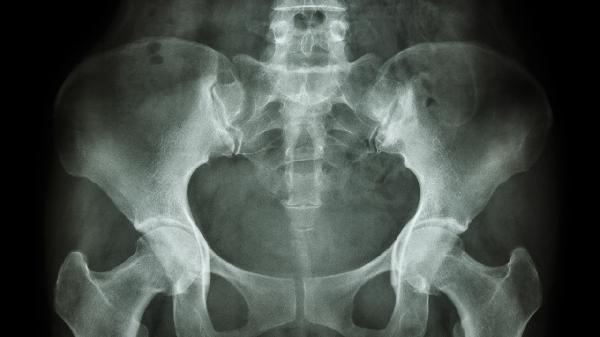

骨盆骨折有哪些常见并发症

骨盆骨折是一种严重的创伤,常由高能量损伤如车祸或高处坠落引起。出血是最常见的并发症之一,由于骨盆区域血管丰富,骨折可能导致大量内出血,严重时甚至危及生命。感染风险也较高,尤其是开放性骨折或手术后的患者,需密切监测伤口情况并使用抗生素预防。神经损伤可能发生在骨折碎片压迫或损伤周围神经时,表现为下肢感觉异常或运动障碍。长期功能障碍包括慢性疼痛、行走困难或骨盆畸形,影响患者的日常活动和生活质量。